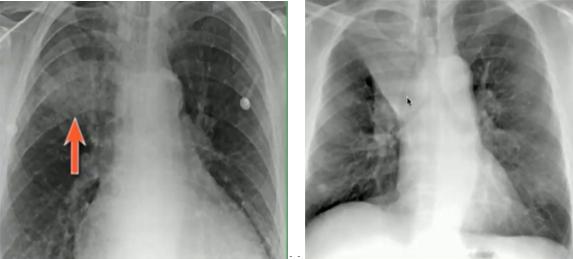

图15.沿肺门分布的线条状阴影,不累及胸膜边界

图16.正位片(左):肺不张(右上肺野肺裂上移);侧位片(右):过度充气(横隔变平)